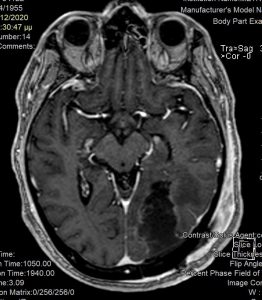

Ασθενής άνδρας, 65 ετών ο οποίος παρουσίασε αρχικά αίσθημα κόπωσης και διαλείπουσες κεφαλαλγίες. Ο νευροαπεικονιστικός έλεγχος με μαγνητική τομογραφία με σκιαγραφικό ανέδειξε χωροκατακτητική εξεργασία στην περιοχή του αριστερού σφηνοειδούς λοβίου με επέκταση και υποεπενδυματική διήθηση του ινιακού κέρατος.

Η μετεγχειρητική μαγνητική τομογραφία εγκεφάλου )βλ. εικόνα) εντός 48ωρου επιβεβαιώνει την ολική εξαίρεση του όγκου.